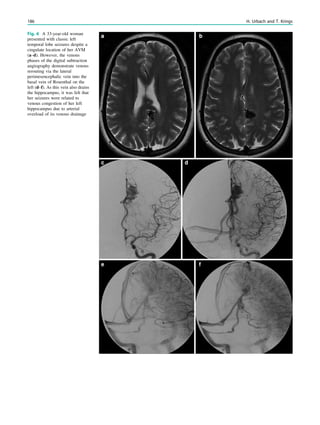

Abstract

This chapter provides Epilepsy-dedicated MRI protocols

and useful informations regarding angulation, spatial

resolution, and contrast to noise ratios.

1 Introduction

Patients with focal (partial) epilepsies in which an epilep-

togenic lesion has not been found (yet) should be studied